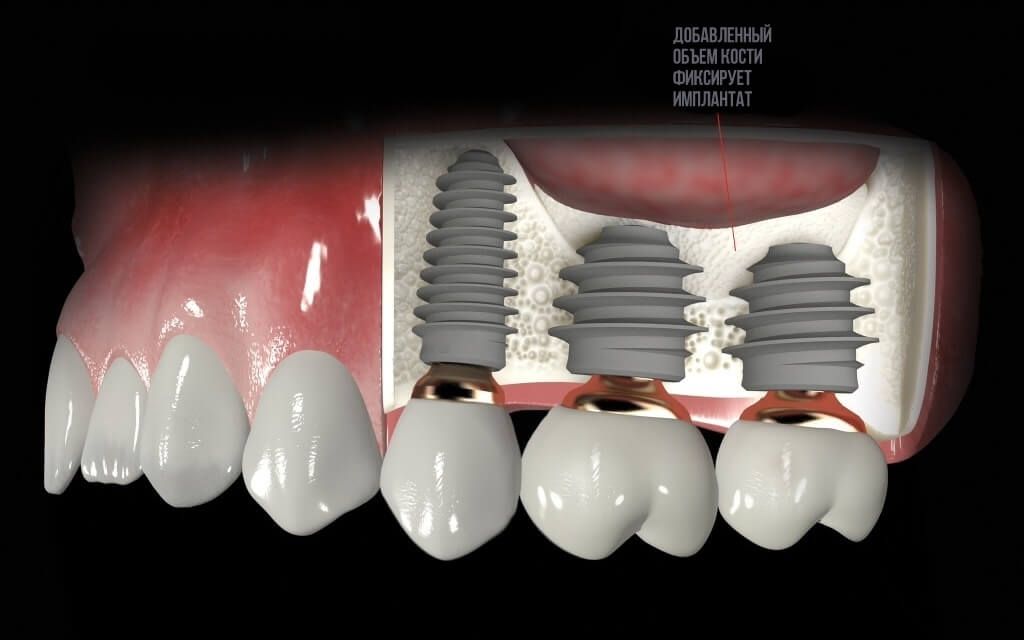

Костная пластика

Увеличение объема кости для надежной пожизненной фиксации в ней имплантата.

Увеличение объема костной ткани для уверенной фиксации имплантата

После удаления зуба из-за отсутствия необходимой нагрузки на челюсть, кость в пустующем месте атрофируется. В этом случае перед имплантацией необходимо восполнить объем костной ткани.